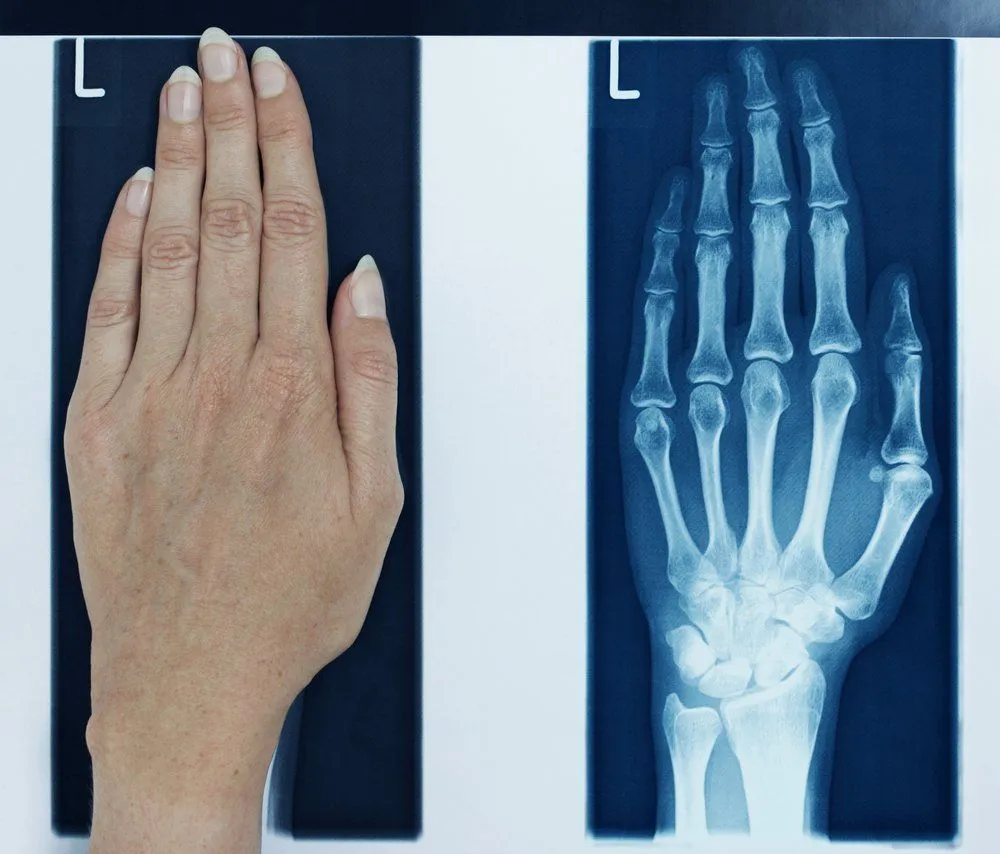

Thanks to movies and pop culture’s love for X-ray vision, we have been led to believe that X-ray vision will let us see through other people’s clothes – as well as buildings and underground bunkers. The truth is, even if you could see through someone’s clothes using your X-ray vision (which, by the way, you can), it’s only their bones that you would be able to see. X-rays have a very small wavelength and high amounts of energy, which is why they can penetrate a lot of stuff to give that ‘see-through’ vision effect.